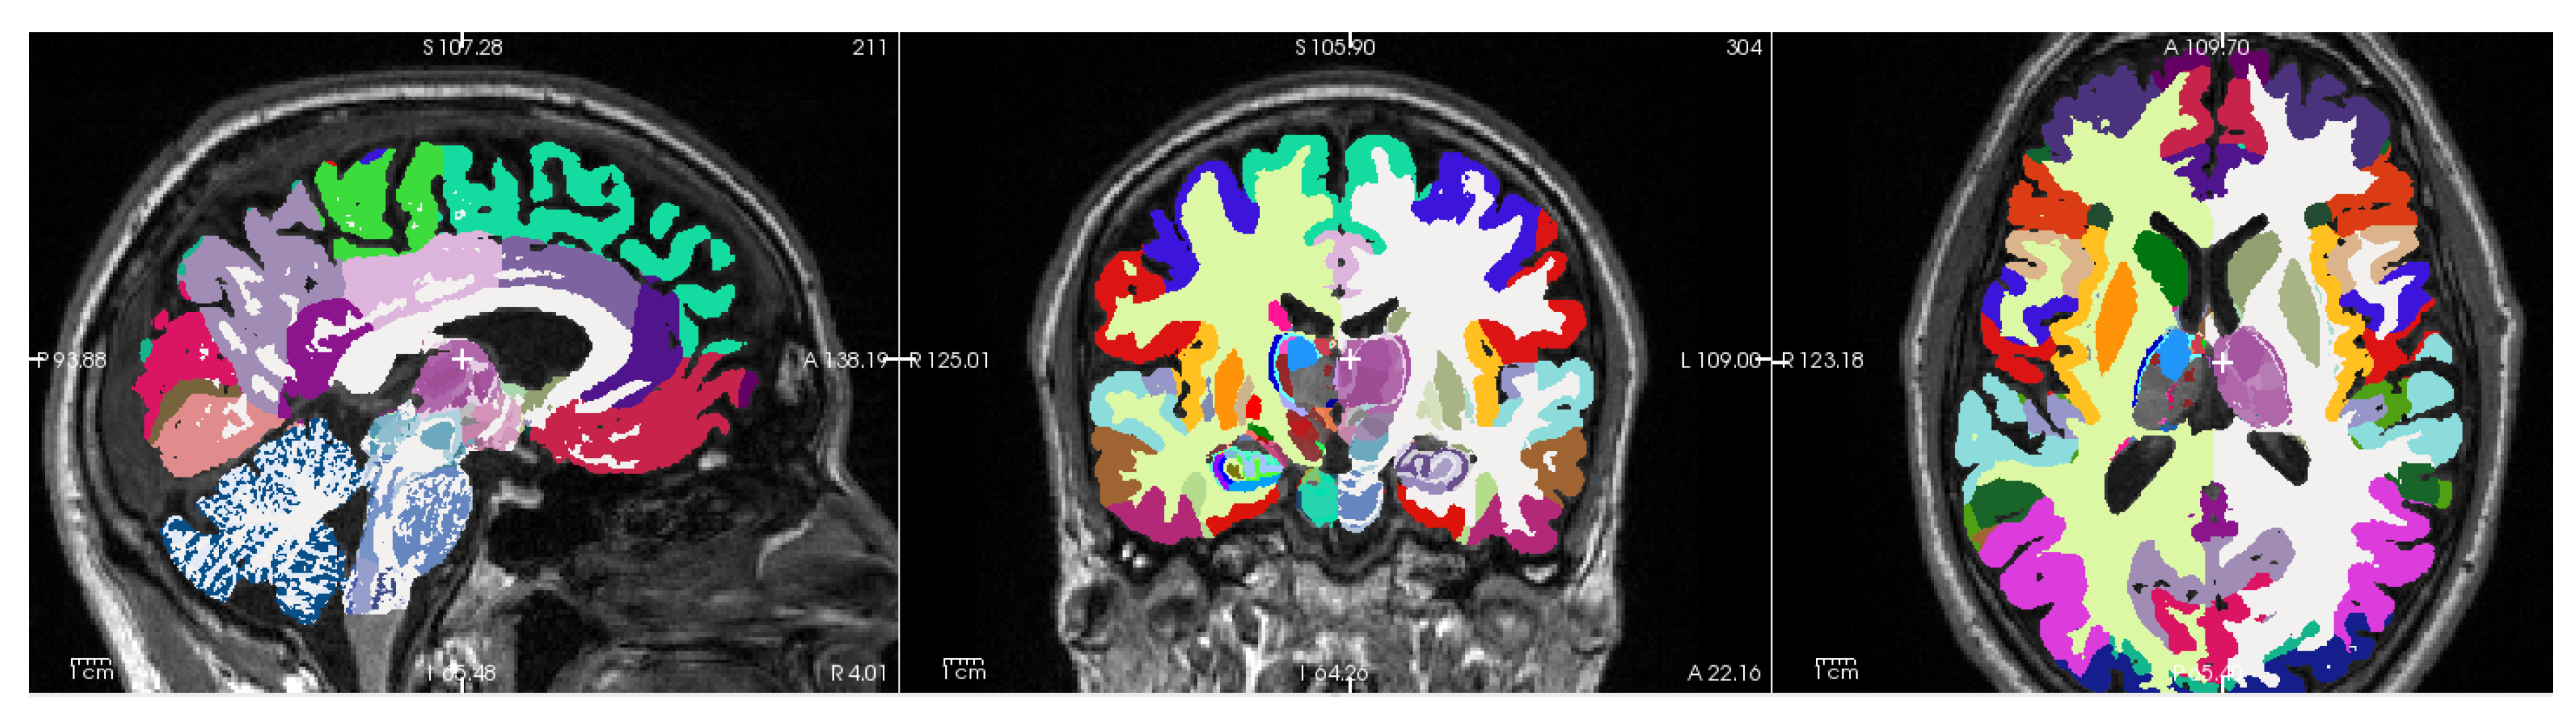

Figure 1 shows a representative T1-weighted image from our dataset, demonstrating the high tissue contrast necessary for accurate morphometric analysis. The corresponding FreeSurfer-generated segmentation mask, which forms the basis for our morphometric measurements, is illustrated in Figure 2. These images exemplify the quality standards maintained throughout our dataset.

Image processing and morphometric analyses were performed using FreeSurfer (https://freesurfer.net), a widely-validated open-source software suite for analyzing brain MRI data [30]. To address both methodological and biological questions, we conducted parallel analyses using two FreeSurfer versions: version 6.0.1, which was employed in the reference study by Skrobisz et al. [23], and the current version 7.4.1.

The evolution of FreeSurfer’s capabilities is particularly relevant to our investigation of brain structure in IBS. Version 7.0 (July 2020) introduced significant improvements in subcortical segmentation accuracy, while version 7.4.1 (June 2023) further enhanced the precision of limbic system structures, notably the hippocampus and amygdala. Additionally, version 7.4.1 provides superior compatibility with multi-modal imaging data and implements refined longitudinal processing algorithms. Since our multimodal MRI examinations were part of a longitudinal IBS intervention study (Berentsen et al. [24]), we also used the longitudinal stream capability of FreeSurfer 7.4.1 to compare baseline longitudinal analysis with a cross-sectional analysis of the first MRI examination.

For both versions, we focused on the automated segmentation of subcortical structures using FreeSurfer’s aseg pipeline, which identifies and quantifies the volume of distinct brain regions (detailed in Table Appendix A.1). This dual-version approach serves two purposes: first, it enables direct comparison with Skrobisz et al.’s [23] findings, and second, it allows us to assess the impact of software evolution on morphometric measurements on a fixed dataset, and differences in cross-sectional and longitudinal stream analysis to discriminate HC and IBS from brain morphometric features. This methodological consideration is crucial, as previous studies have demonstrated that version-dependent variations in automated segmentation can significantly influence morphometric results [31,32,33,34,35,36]. By analyzing our data with both versions, we can distinguish between genuine biological differences and methodologically-induced variations in brain morphometry.

The enhanced accuracy of version 7.4.1 is particularly relevant for our investigation of IBS, as it provides more reliable quantification of brain regions implicated in visceral sensation, pain processing, emotional regulation, and cognitive function.

We will also like to add that in vivo brain segmentation technologies move very fast. Recently (November 2024), the FreeSurfer 8.0.0-beta version enables histological super granularity with identification and volume measurements from more than 300 distinct regions per hemisphere (cf. Figure A2). The aseg mask provides less than 40 brain regions and their volumes within the intracranial space.